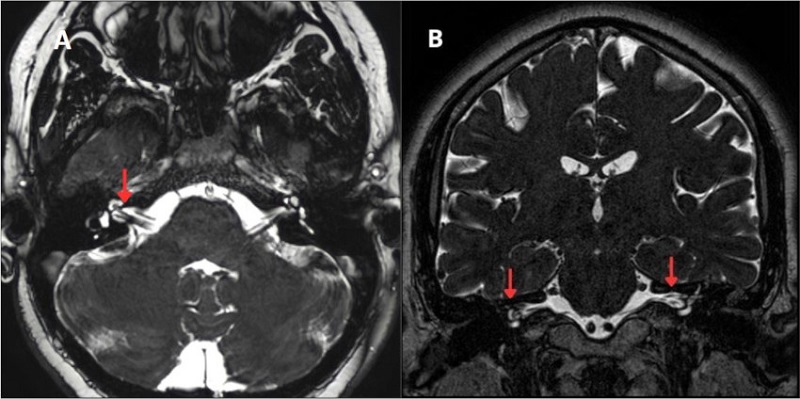

Se utilizó el sistema Chavda para definir la extensión del loop vascular (Fig. 3). La clasificación se compone por tres tipos: el tipo I es un loop vascular situado en el ángulo pontocerebeloso, que no ingresa al CAI

(Fig. 4); el tipo II loop vascular ingresa, pero sin extensión mayor del 50% de la longitud del CAI (Fig. 5), y el tipo III loop vascular con extensión mayor del 50% de la longitud del CAI (Fig. 6)8.

Según la clasificación anatómica Chavda (Fig. 3), el tipo de loop vascular más frecuente es el tipo I de oído (derecho: 52,6%; izquierdo: 33,3% y bilateral: 14,1%) (Fig. 4 A y B), seguido del tipo II de oído (derecho: 31,3%; izquierdo: 37,5% y bilateral: 31,3%) (Fig. 5 A y B) y el tipo III de oído (derecho: 50,0%; izquierdo: 25,0% y bilateral: 25,0%) (Fig. 6 A y B) (Fig. 9).